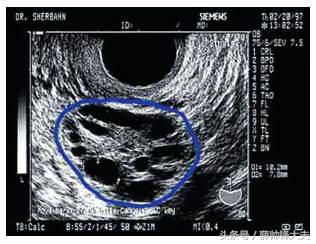

所谓“多囊”医学上主要是指超声下提示的双侧卵巢内窦卵泡数目的增多,呈多囊样改变,但不一定会引起一系列的临床症状及表现。而我们真正的病例性“多囊”更确切的来说指的是“多囊卵巢综合征PCOS”,而这个属于疾病性表现,不单纯的卵巢呈多囊样改变,于此同时会表现会一系列内分泌失调的表现,如:肥胖,体毛增多,月经稀发或闭经,雄激素增高,体内激素LH/FSH比值>1:2,更严重的伴随有一些列内分泌失调的症状等。所以如果单纯的超声多囊样改变和病例性的多囊卵巢综合征不能一概而论混为一谈。所以对于广大女性朋友需要明确一下自己是单纯的“多囊”还是“多囊卵巢综合征”。如果是单纯的多囊样改变,没有其他的伴随症状,就不是“多囊卵巢综合征”,大可放心,不必处理。